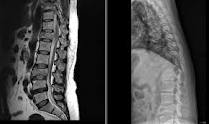

Иногда применяются визуализирующие методы исследования, позволяющие получить больше информации о нарушениях в области спины. К визуализирующим методам исследования нарушений в области спины относятся: магнитно-резонансная томография (МРТ), компьютерная томография (КТ), сканирование костей и рентгенологическое исследование. Если результаты Вашего обследования предполагают наличие у Вас серьезного заболевания, Ваши симптомы длятся более 4-6 недель, или у Вас отмечается постоянная сильная боль в спине, боль или онемение в ноге, визуалиризирующие методы исследования могут пролить свет на Ваше заболевание и его причины.

- МРТ и компьютерная томография в равной степени способны могут дать точную визуализацию грыжи диска или стеноза позвоночного канала, которые могут вызвать нарушения, связанные со сдавлением нервов. МРТ имеет преимущество перед компьютерной томографией в том отношении, что при МРТ не используется ионизирующее облучение.

Протрузия или грыжа диска может сдавливать нерв в том месте, где у Вас сзади от спинного мозга отходят нервные веточки. Такое сдавление может вызывать боль, онемение, покалывание, слабость или утрату рефлексов в ноге. Она может вызывать боль в пояснице, а может и нет. Однако во многих случаях грыжа диска не вызывает никаких симптомов. Если МРТ-исследование показало у Вас наличие грыжи диска, Ваш доктор тщательно сопоставит результаты МРТ с результатами Вашего медицинского осмотра для того, чтобы убедиться в том, что визуализируемая на МРТ грыжа диска является наиболее вероятной причиной Ваших симптомов.

- Такие диагностические методы исследования, как магнитно-резонансная томография (МРТ), компьютерная томография указывают на то, что Ваша грыжа диска может быть излечена хирургически.